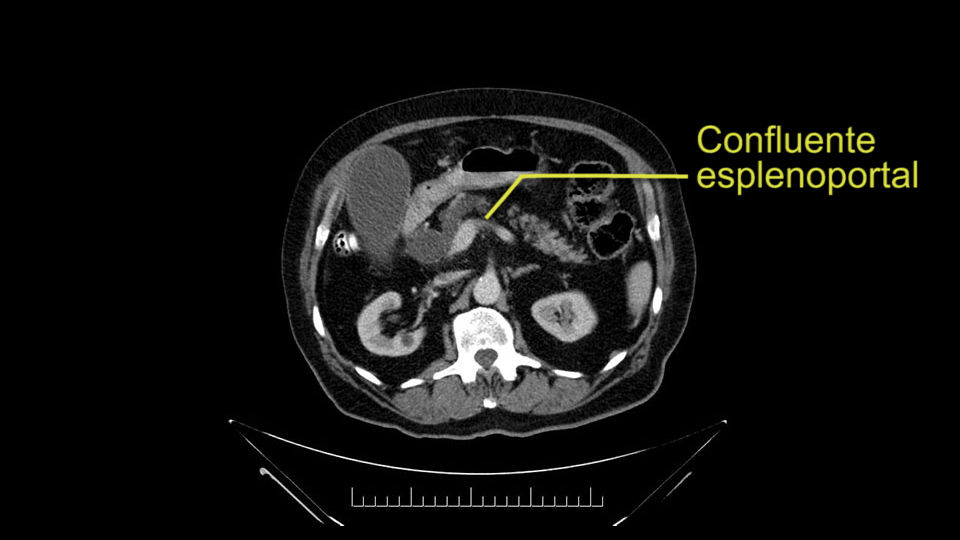

The next item that I would look at: the issue would be the vessels and usually start at the portal vein, watch the portal vein, follow it down, down-down-down to the neck of the pancreas - which is here - and there’s no impingement by tumor, which is great. The SMV and the splenic vein, which is here. The splenic vein junction is normal, which is great.

The next thing we always evaluate, although we do not expect invasion to the portal veins in this case, we must always trace the path of the portal vein, in both directions, from top to bottom. The splenoportal confluence and the superior mesenteric vein, which in this case does not appear to be compromised.

Por otro lado, siempre evaluamos -aunque en este caso no esperamos que haya invasión de los vasos portales-, siempre hay que hacer el recorrido de la vena porta, en ambos sentidos, de arriba hacia abajo; el confluente esplenoportal y la vena mesentérica superior, que en este caso no aparentan estar comprometidos.